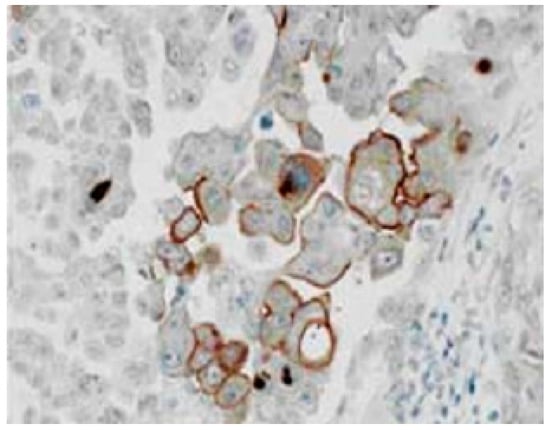

3.1. Immuhohistological Expressions of PEPT1 and ABCG2 Protein

- Yonemura, Y.; Endo, Y.; Canbay, E.; Liu, Y.; Ishibashi, H.; Takeshita, K.; Mizumoto, A.; Hirano, M.; Takao, N.; Ichinose, M.; et al. Selection of patients by membrane transporter expressions for aminolevulinic acid (ALA)-guided photodynamic detection of peritoneal metastases. Int. J. Sci. 2015, 4, 66–77. [Google Scholar] [CrossRef]

- Hagiya, Y.; Fukuhara, H.; Matsumoto, K.; Endo, Y.; Nakajima, M.; Tanaka, T.; Okura, I.; Kurabayashi, A.; Furihata, M.; Inoue, K.; et al. Expression levels of PEPT1 and ABCG2 play key roles in 5-aminolevulinic acid (ALA)-induced tumor-specific protoporphyrin IX (PpIX) accumulation in bladder cancer. Photodiag. Photodyn. Ther. 2013, 10, 288–295. [Google Scholar] [CrossRef]

- Hagiya, Y.; Endo, Y.; Yonemura, Y.; Takahashi, K.; Ishizuka, M.; Abe, F.; Tanaka, T.; Okura, I.; Nakajima, M.; Ishikawa, T.; et al. Pivotal roles of peptide transporter PEPT1 and ATP-binding cassette (ABC) transporter ABCG2 in 5-aminolevulinic acid (ALA)-based photocytotoxicity of gastric cancer cellsin vitro. Photodiag. Photodyn. Ther. 2012, 9, 204–214. [Google Scholar] [CrossRef] [PubMed]